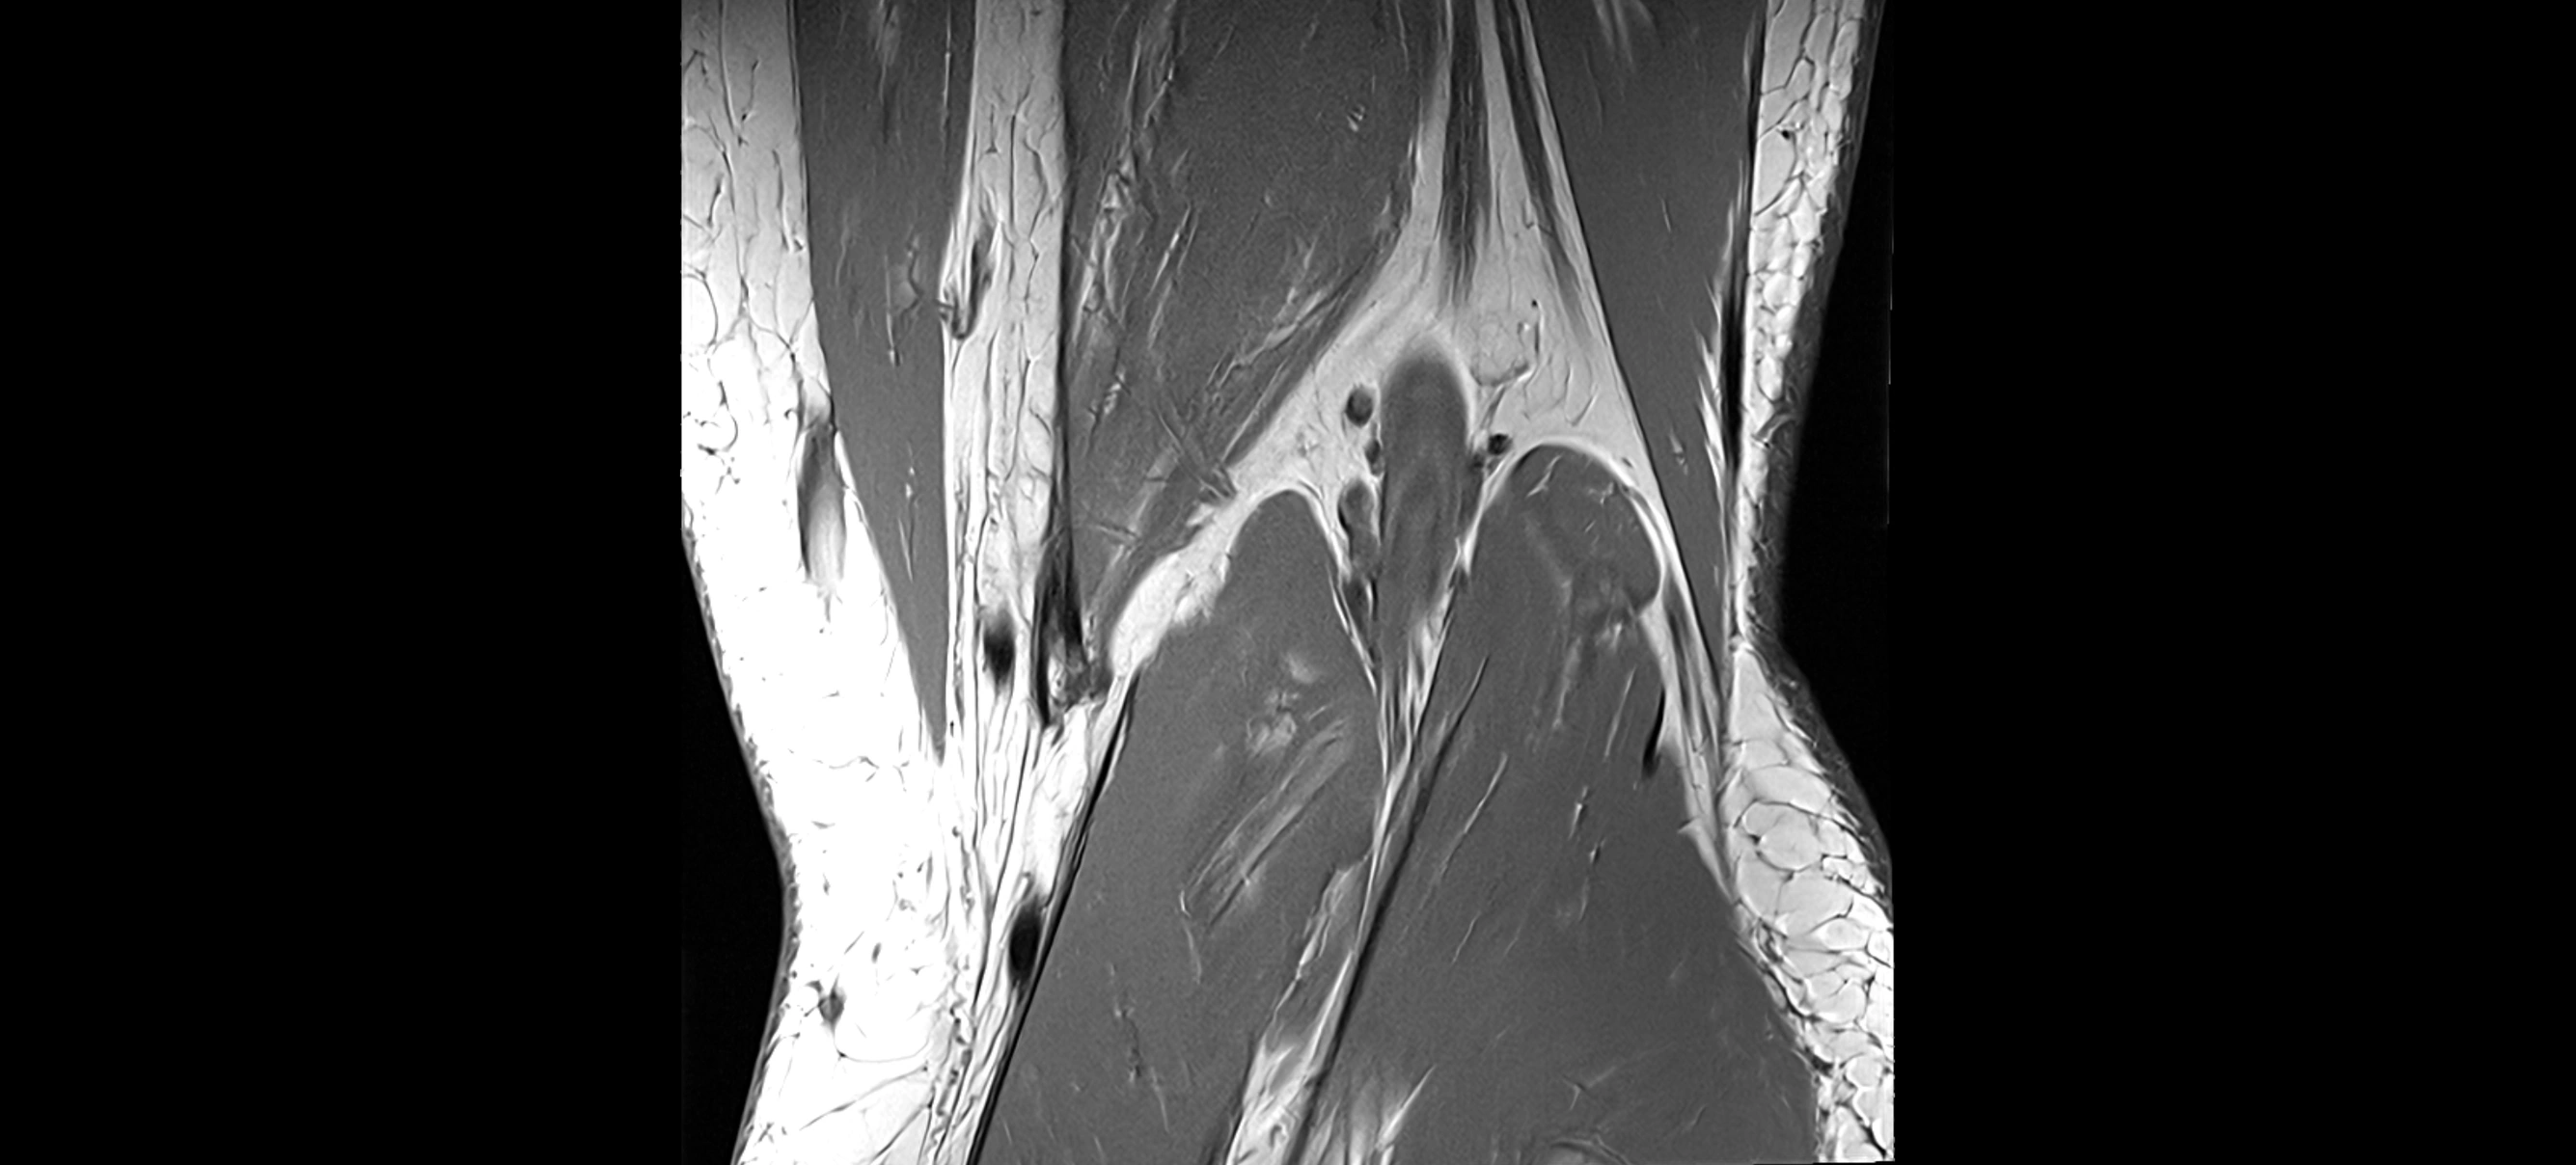

MRI images

image

MRI Appearance

T1-weighted images:

• Normal ACL appears as a low-signal band-like structure crossing the intercondylar notch

• Surrounded by intermediate signal synovial fluid and fat planes

T2-weighted images:

• Normal ACL remains low signal

• Partial or complete tears appear as discontinuity, increased signal, or fiber laxity